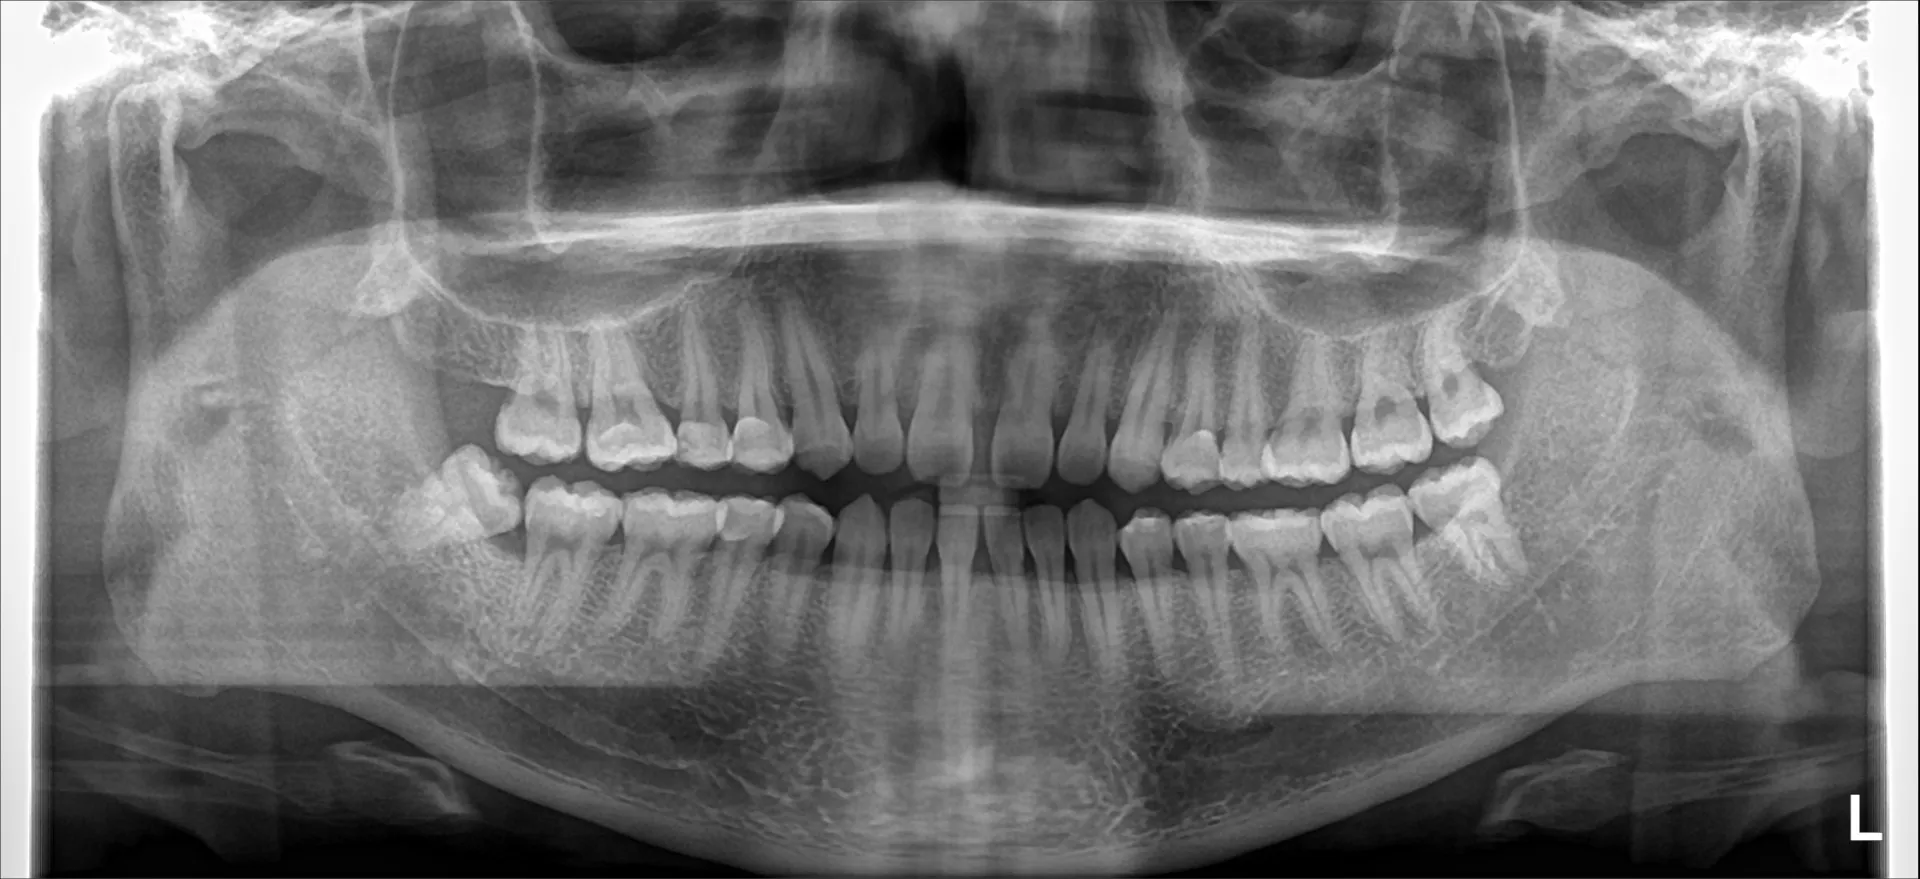

今回はよく質問される「親知らずはこの歯医者で抜けますか?」について簡単にご紹介いたします。

まずはじめに、基本どの歯医者さんでも比較的対応している親知らずの抜歯があります。

それは真っすぐ生えた上の親知らずです。

特に若い方で女性で歯の根っこが1本となるとより抜歯の難易度が下がる傾向があります。

当院ではかなりのハイリスク親知らず出ない場合には抜歯の対応を行っております。